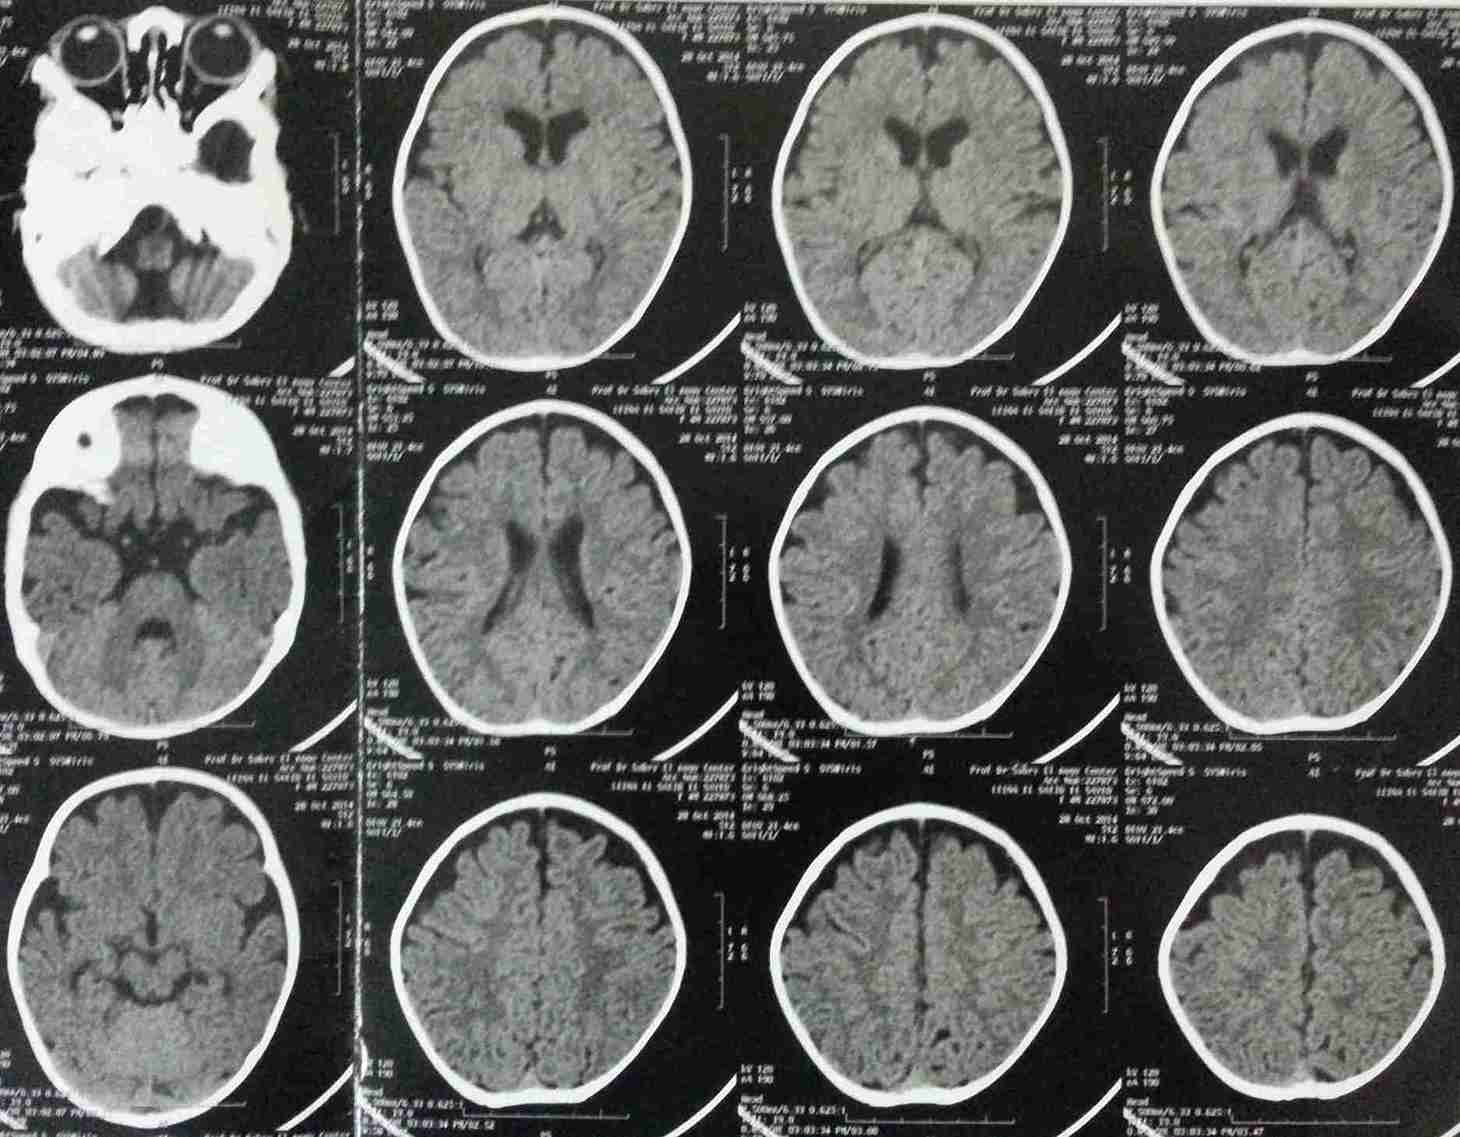

premature closure of the coronal sutures with a small forehead in a 4-month-old girl